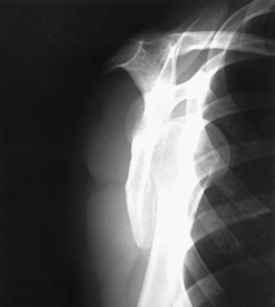

This projection, described by Rubin et al.,1 obtained its name as a result of the appearance of the scapula. The body of the scapula forms the vertical component of the Y, and the acromion and coracoid processes form the upper limbs. This projection is useful in the evaluation of suspected shoulder dislocations.

Structures shown: The scapular Y is shown on an oblique image of the shoulder. In the normal shoulder, the humeral head is directly superimposed over the junction of the Y (Fig. 5-37). In anterior (subcoracoid) dislocations, the humeral head is beneath the coracoid process (Fig. 5-38); in posterior (subacromial) dislocations, it is projected beneath the acromion process. An AP shoulder projection is shown for comparison (Fig. 5-39).

Fig. 5-38 PA oblique shoulder joint showing anterior dislocation (humeral head projected beneath coracoid process).

Fig. 5-39 AP shoulder (same patient as in Fig. 5-38).